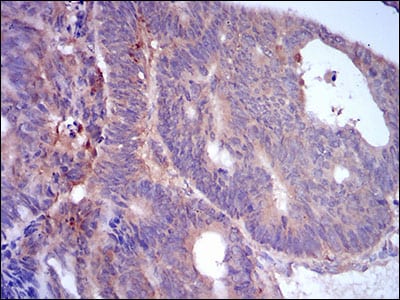

Immunohistochemical analysis of paraffin-embedded human rectum cancer tissues using PLIN2 mouse mAb with DAB staining.